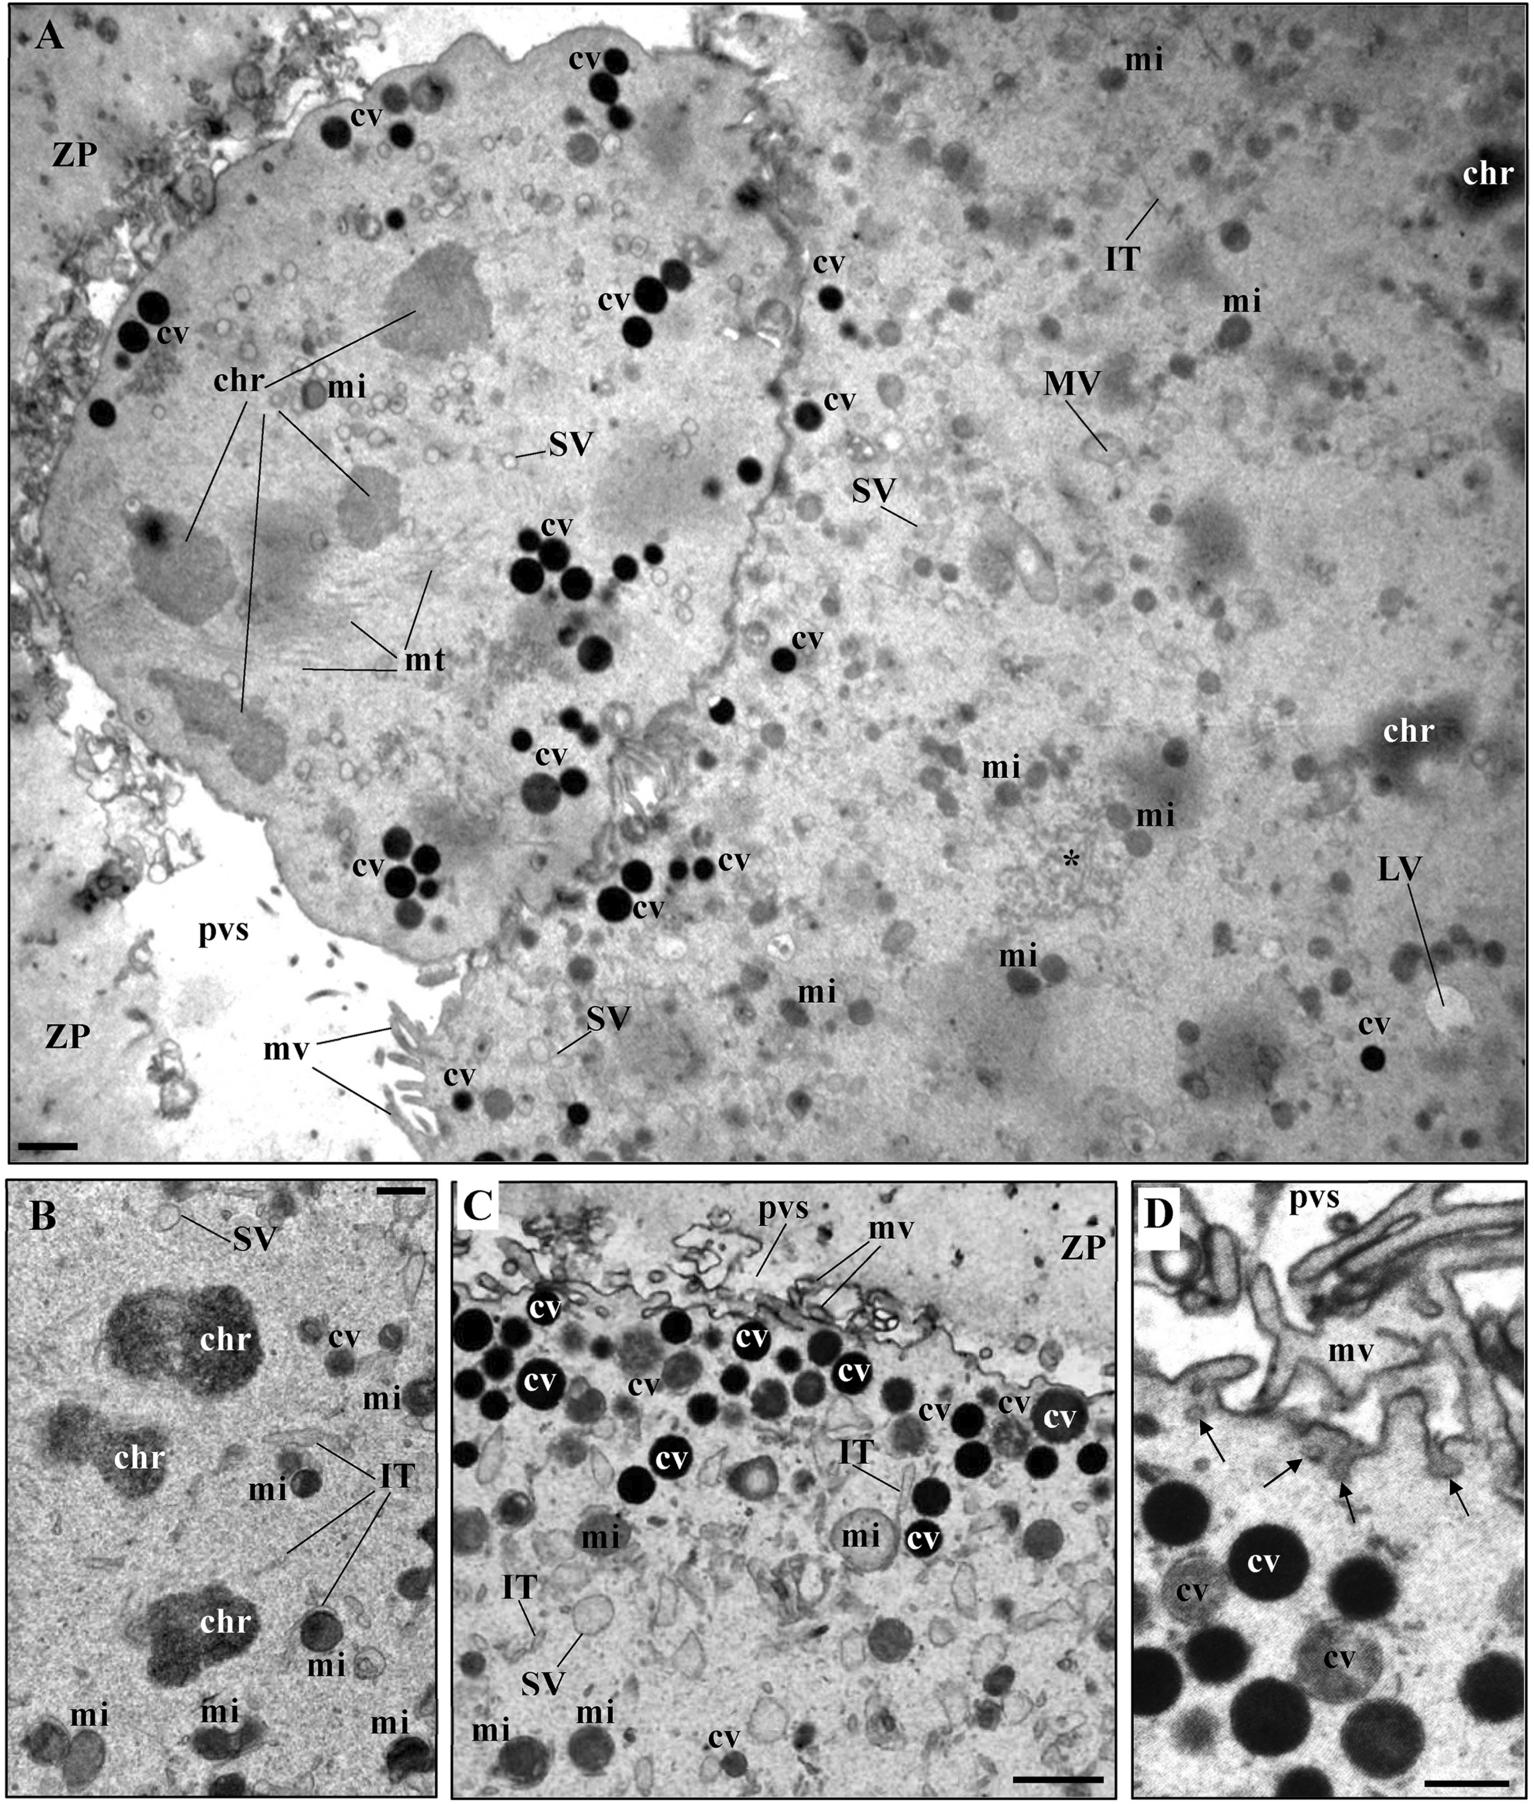

Fig. 2

From: Stereological study of organelle distribution in human mature oocytes

Ultrastructural images of metaphase-II oocytes. (A) First polar body (PB1), showing chromosomes (chr), chromosomal microtubules (mt), mitochondria (mi), smooth endoplasmic reticulum (SER) small vesicles (SV) and cortical vesicles (cv). The PB1 is inserted in the perivitelline space (pvs), between the zona pellucida (ZP) and the oolemma. The oocyte surface contained microvilli (mv), outside the PB1 apposition region. In the ooplasm it can be observed cortical vesicles (cv), mitochondria (mi), smooth endoplasmic reticulum (SER) small (SV), medium (MV) and large (LV) vesicles, SER isolated tubules (IT), and SER small tubular aggregates (*). (A, B) Oocyte chromosomes (chr) at the metaphase-II plate. (A, C, D) Cortical vesicles (cv) were observed to form layers under the oolemma, with some presenting decondensed contents. (D) Tiny coated-vesicles (arrows) were observed at the oocyte surface. Bars: (A, B, C) 1 μm; (D) 0.5 μm.